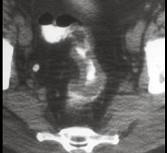

问题 男,53岁,便秘、血便,大便变细,CT如图,应考虑为 ( )

选项 A.肠Crohn病 B.直肠结核 C.溃疡型直肠癌 D.慢性溃疡性结肠炎 E.直肠淋巴瘤

答案 C